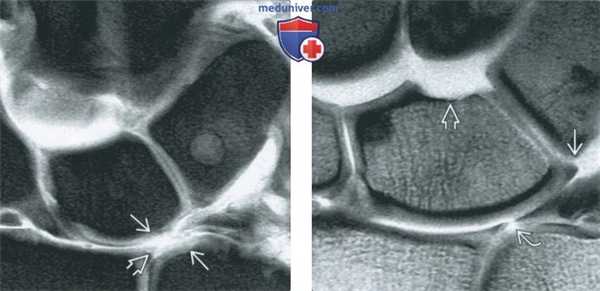

(Слева) МР-артрография в режиме Т1ВИ FS, коронарный срез, этот же пациент: визуализируются поврежденные волокна тыльной межзапястной и лучетрехгран-нойВ связок.

(Справа) МР-артрография в режиме PD FS, сагиттальный срез, пациент, перенесший перелом дистального отдела лучевой костив: визуализируется отрыв небольшого костного фрагмента за счет тяги луче-полулунной связки.